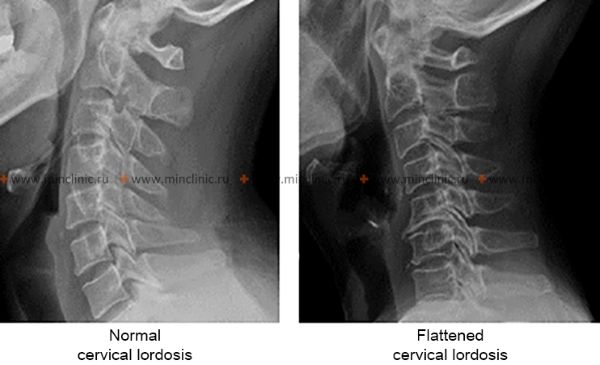

- X-ray of the Cervical Spine: Often performed with functional tests (flexion and extension views) to assess for degenerative changes (osteophytes, disc space narrowing, facet arthropathy), alignment (e.g., straightening or reversal of normal cervical lordosis), and instability.

A lateral radiograph of the cervical spine can indicate changes in the normal cervical lordosis (inward curve), such as an excessively pronounced curve (hyperlordosis) or a smoothed, straightened curve (loss of lordosis), which can be associated with neck pain.